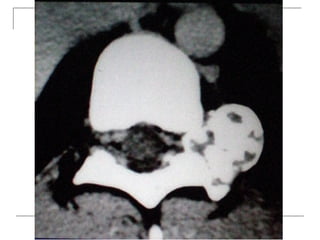

CT Scan

 better visualization of bone pathology (eg.

cortical destruction)

 fracture

 tumor